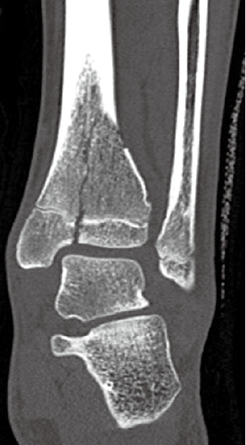

脛骨遠位骨端線損傷

脛骨遠位骨端線が閉鎖する時期に限定されます。Triplane 骨折は12~15 歳頃に好発する骨折で、脛骨の骨端線の閉鎖時期と閉鎖の仕方に関係しているとされています。

(図18) Triplane 骨折 左 レントゲン 右CT画像

(図18)MB Orthop. 38(5):55—64,2025大人とこどものスポーツ外来 下肢編【こども編】小児アスリートの足関節・足部捻挫に対する外来診療 田中 博史より抜粋

(図19)整形外科Surgical Technique vol.12 no.5 2022 52‐57(604‐609)[手術法] こどもの足関節周囲骨折・ Juvenile Tillaux・Triplane骨折 依光正則 より抜粋一部変更

Triplane 骨折は、Salter-Harris分類ではⅣ型にあてはまります。Ⅲ型は、Tillaux骨折といいます。脛骨遠位端骨折はⅠ/Ⅱ型が50%、Ⅲ型が25%、Ⅳ型が10%の頻度で発生するとされています。手術適応はⅡ~Vで考慮されます。Ⅴは骨端線がつぶれた状態です。